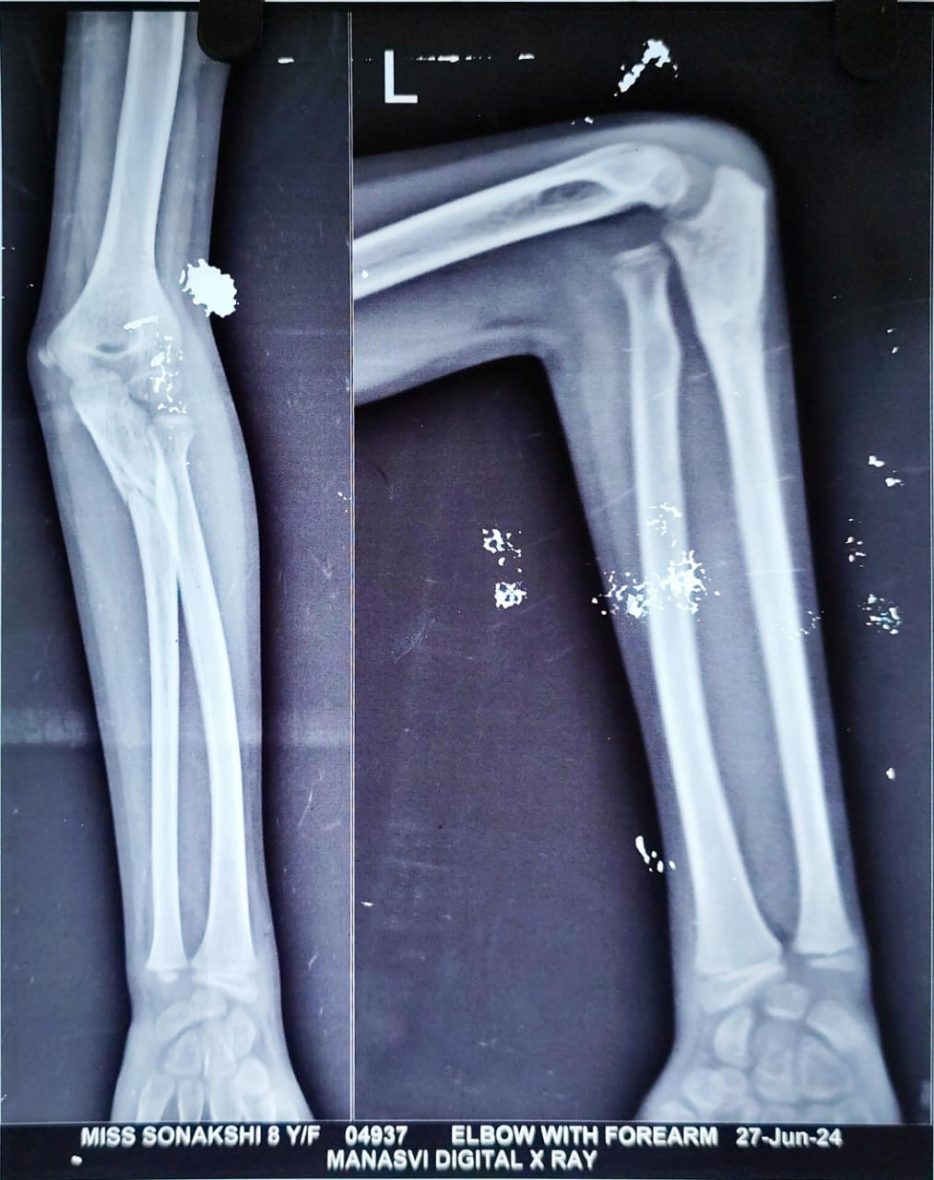

Radiographs of the left forearm and elbow (anteroposterior and lateral views) revealed a uniting fracture of the proximal ulna with anterior dislocation of the radial head (Fig. 1) – findings consistent with a Bado type I Monteggia lesion. Given the history of trauma, absence of early imaging, and delayed presentation, a diagnosis of neglected Monteggia fracture-dislocation was made. Advanced imaging was not done as the radiographs were indicative of a Monteggia lesion in a 1-month-old injury. Radiographs were analyzed by methods as described by Lincoln and Mubarak, including the ulnar bow sign and the radiocapitellar line of McLaughlin [7].

Figure 1: Monteggia fracture dislocation left elbow (1-month-old).